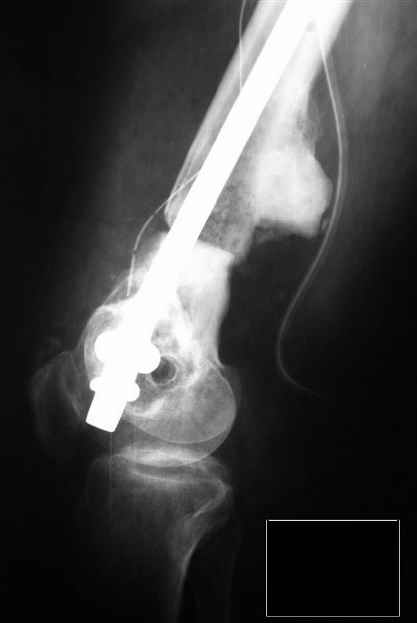

Произвели операцию на левом бедре. Остеотомия параоссальной мозоли, репозиция отломков "конец в конец", с хорошим полным контактом, остеосинтез ретроградным бедренным гвоздём ChM.

Длина сегмента восстановлена практический полностью, устранена угловая деформация. Если будет мешать разработке, через месяц планируем "утопить" гвоздь глубже и резецировать избыток параоссальной ткани по задней поверхности бедра. Рахматуллин Ринат Нургаянович ГКБ N13 г.Уфа.